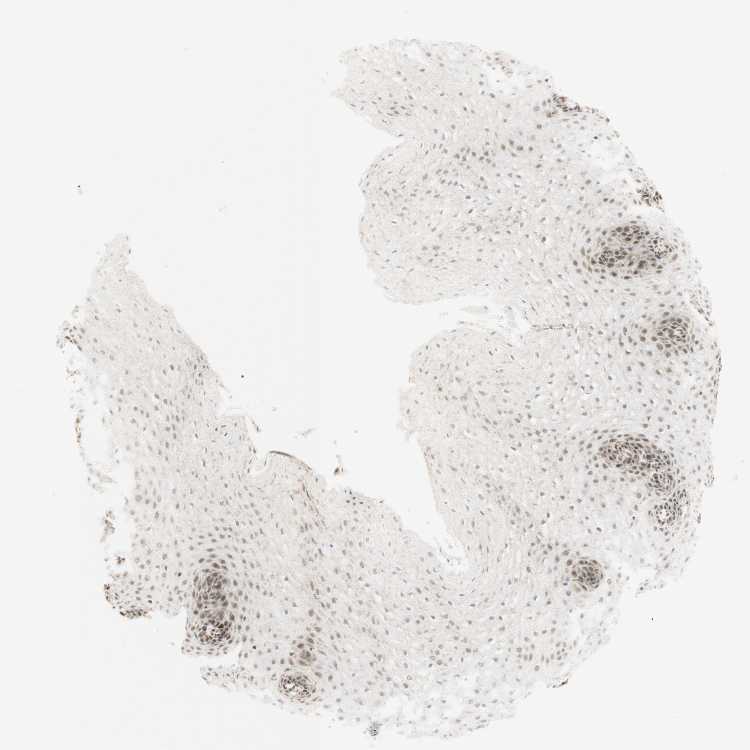

ESOPHAGUS - Antibody stainingi

Antibody staining in the annotated cell types in the current human tissue is reported as not detected, low, medium, or high, based on conventional immunohistochemistry profiling in selected tissues. This score is based on the combination of the staining intensity and fraction of stained cells.

Each image is clickable and will lead to virtual microscopy that enables deeper exploration of all samples and also displays staining intensity scores, fraction scores and subcellular localization as well as patient and tissue information for each sample.

Antibody HPA011013

Squamous epithelial cells Medium